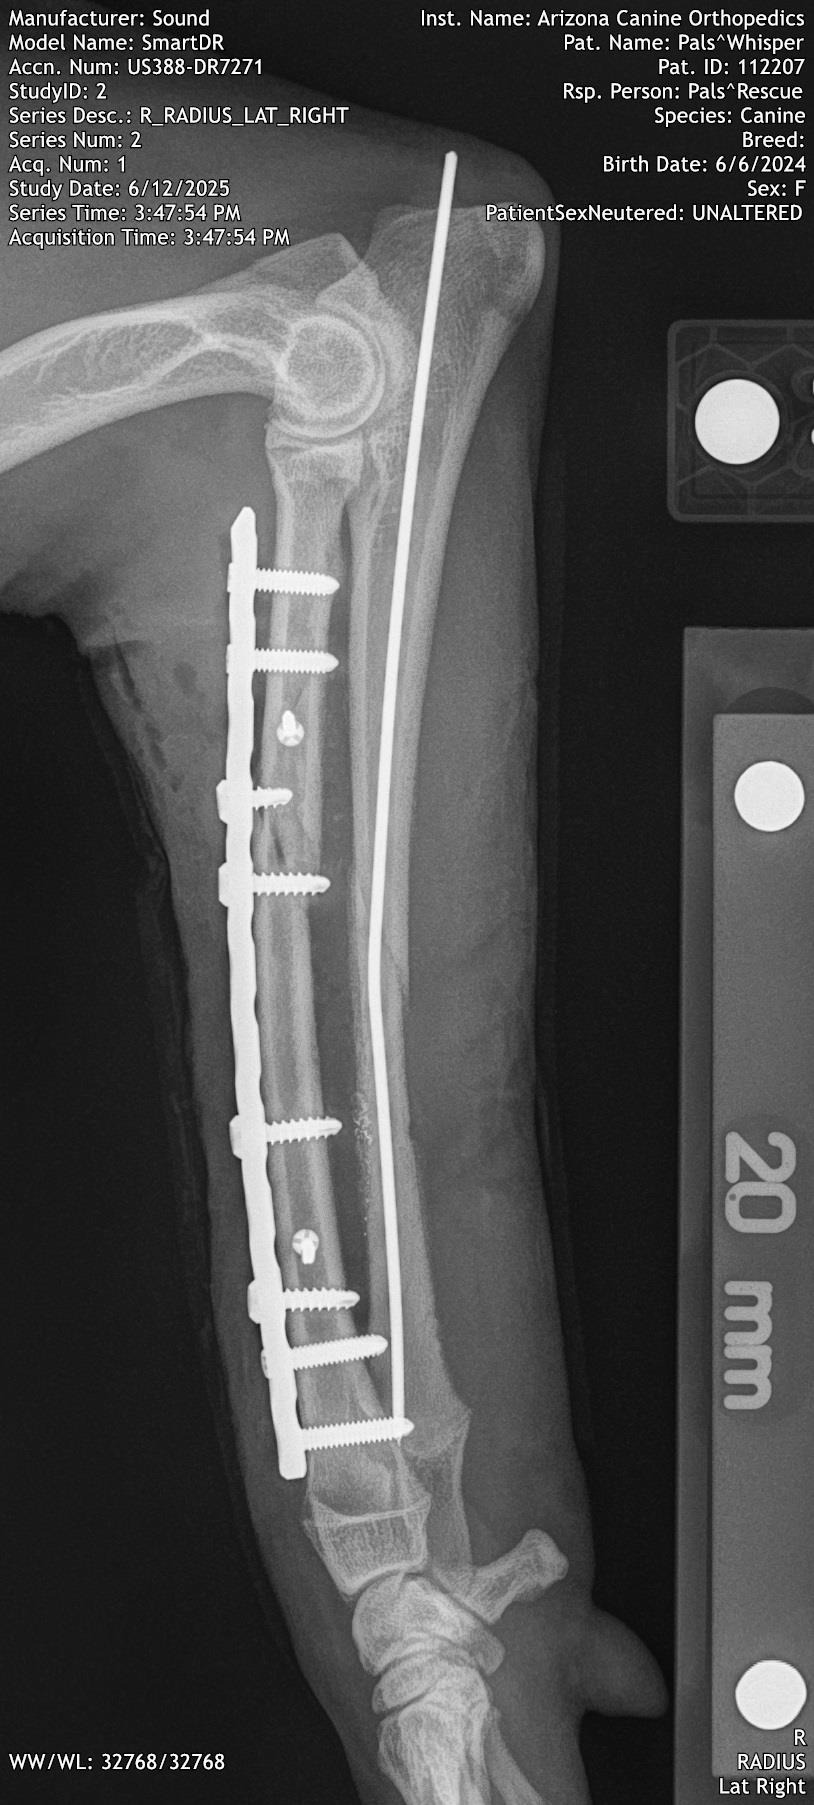

Because Whisper is under a year old and in good health, we decided to try and see if her leg could be saved. Dr. Hoban contacted Dr. Lirtzman of ACOSM and he agreed to try and save Whisper's leg.

On Thursday 6/16 she went in for a long but successful surgery.

On Friday 6/17 Whisper went to her foster home where she is recovering extremely well.